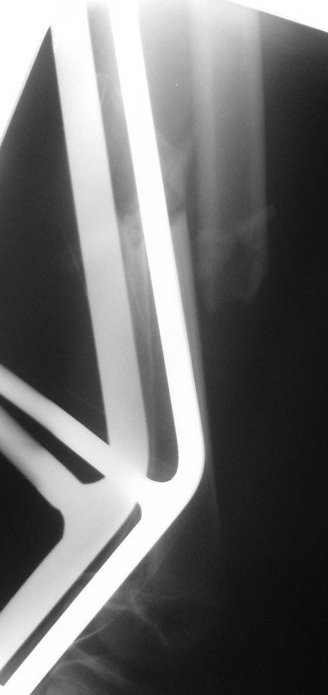

Это снимки при поступлении, похоже.

Я бы сделал свежие. Пока предполагаю, что раз срок большой, возраст маленький, то, вероятно, лучше в два этапа - - аппаратом растянуть за неделю, а потом заштифтовать. Раз старше 12 лет, то согласен с Марком, не TENами, а нетолстым ригидным стержнем с латерализованным проксимальным отделом. Зона роста если и пострадает, то всего одна, и за оставшейся период роста не успеет сформироваться разница длин.